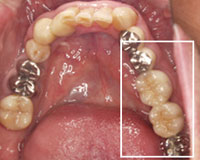

治療後の上の歯

インプラントを埋入後、かみ合わせ部分には金属を使用。

一番奥の歯を金属とし、支えをつけた

治療後の下の歯

インプラント埋入後、セラミックと金属 を使用.